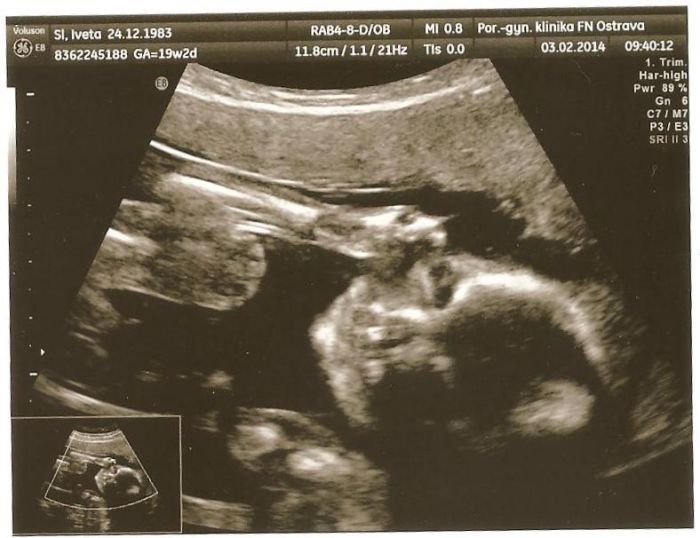

Tak jsem byla na velkém Utz a vše je v pořádku. Akorát mám pupečníkovou šňůru v cestě, doufám, že ještě povyleze. Váha 260 g, velikost asi 20 cm. A je to holčička

Takže Radko můžeš do tabulky napsat první dítě, holčička Leontýnka a město Havířov.